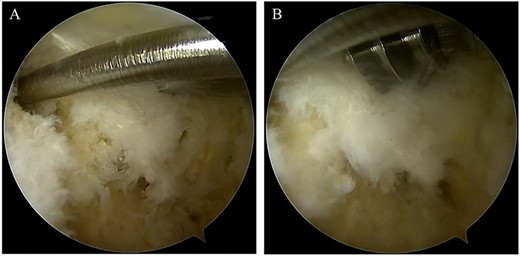

A 76-year-old female, who worked as a cleaner, complained of pain in her right ankle when going downstairs while working. She had medical history of only osteoporosis and had taking daily active vitamin D for >10 years. She was given conservative treatment for 1 month at a local clinic, however, her ankle pain persisted and so she visited our clinic. Physical examinations revealed tenderness and swelling at the anterior aspect of the ankle. Plain radiographs showed no obvious abnormal findings (Fig. 1). Magnetic resonance imaging (MRI) revealed a low signal linear line in the talar neck and a bone marrow edema around the line (Fig. 2). Non-contrast computed tomography (CT) demonstrated an obvious fracture line in the talar neck, however, the bone fragment was not displaced (Fig. 3). Based on medical histories, clinical and radiological findings, we diagnosed her with a fragility fracture of the talar neck associated with osteoporosis. Because the patient was elderly and it was difficult to treat using a prolonged non-weightbearing cast, we applied operative treatment to allow early rehabilitation. The operation was performed under spinal anesthesia in a prone position with an air tourniquet and a fluoroscopy. The posteromedial and posterolateral portals were created according to van Dijk et al. [10]. First, the posterior aspect of the talus was observed using a 4.0-mm diameter 30° arthroscope, and soft tissues around the talus (including synovium and adipose tissues) were removed with a 3.5-mm diameter motorized shaver. After confirming the posterior part of the talar body and the FHL, two 1.6-mm diameter guidewires were parallelly inserted from the posterior part of the talar body to the talar head by hindfoot endoscopy and fluoroscopy (Fig. 4A), and two cannulated 4.5-mm diameter double-threaded screws (Double Thread Screw, Meira, Nagoya, Japan) were inserted through the guidewires (Fig. 4B). The wound was sutured, and the operation was concluded (Fig. 5). Active range of motion exercises were allowed immediately after surgery, and a non-weightbearing short leg splint was worn for 1 week. Partial-weight bearing was permitted at 2 weeks and full-weight bearing was permitted at 4 weeks post-operatively. In addition, daily injections of teriparatide (Forteo, Eli Lilly and Company, Indianapolis, IN, USA) were introduced 2 weeks post-operatively. Eight weeks after the operation, the patient was able to return to work without pain or functional impairment. One year postsurgery, the patient was still working as a cleaner without any symptoms or complications.

(A) After confirming the posterior part of the talar body and the FHL, two 1.6-mm diameter guidewires were parallelly inserted from the posterior part of the talar body to the talar head via under hindfoot endoscopy and fluoroscopy; (B) two cannulated, 4.5-mm diameter double-threaded screws were inserted through the guidewires.